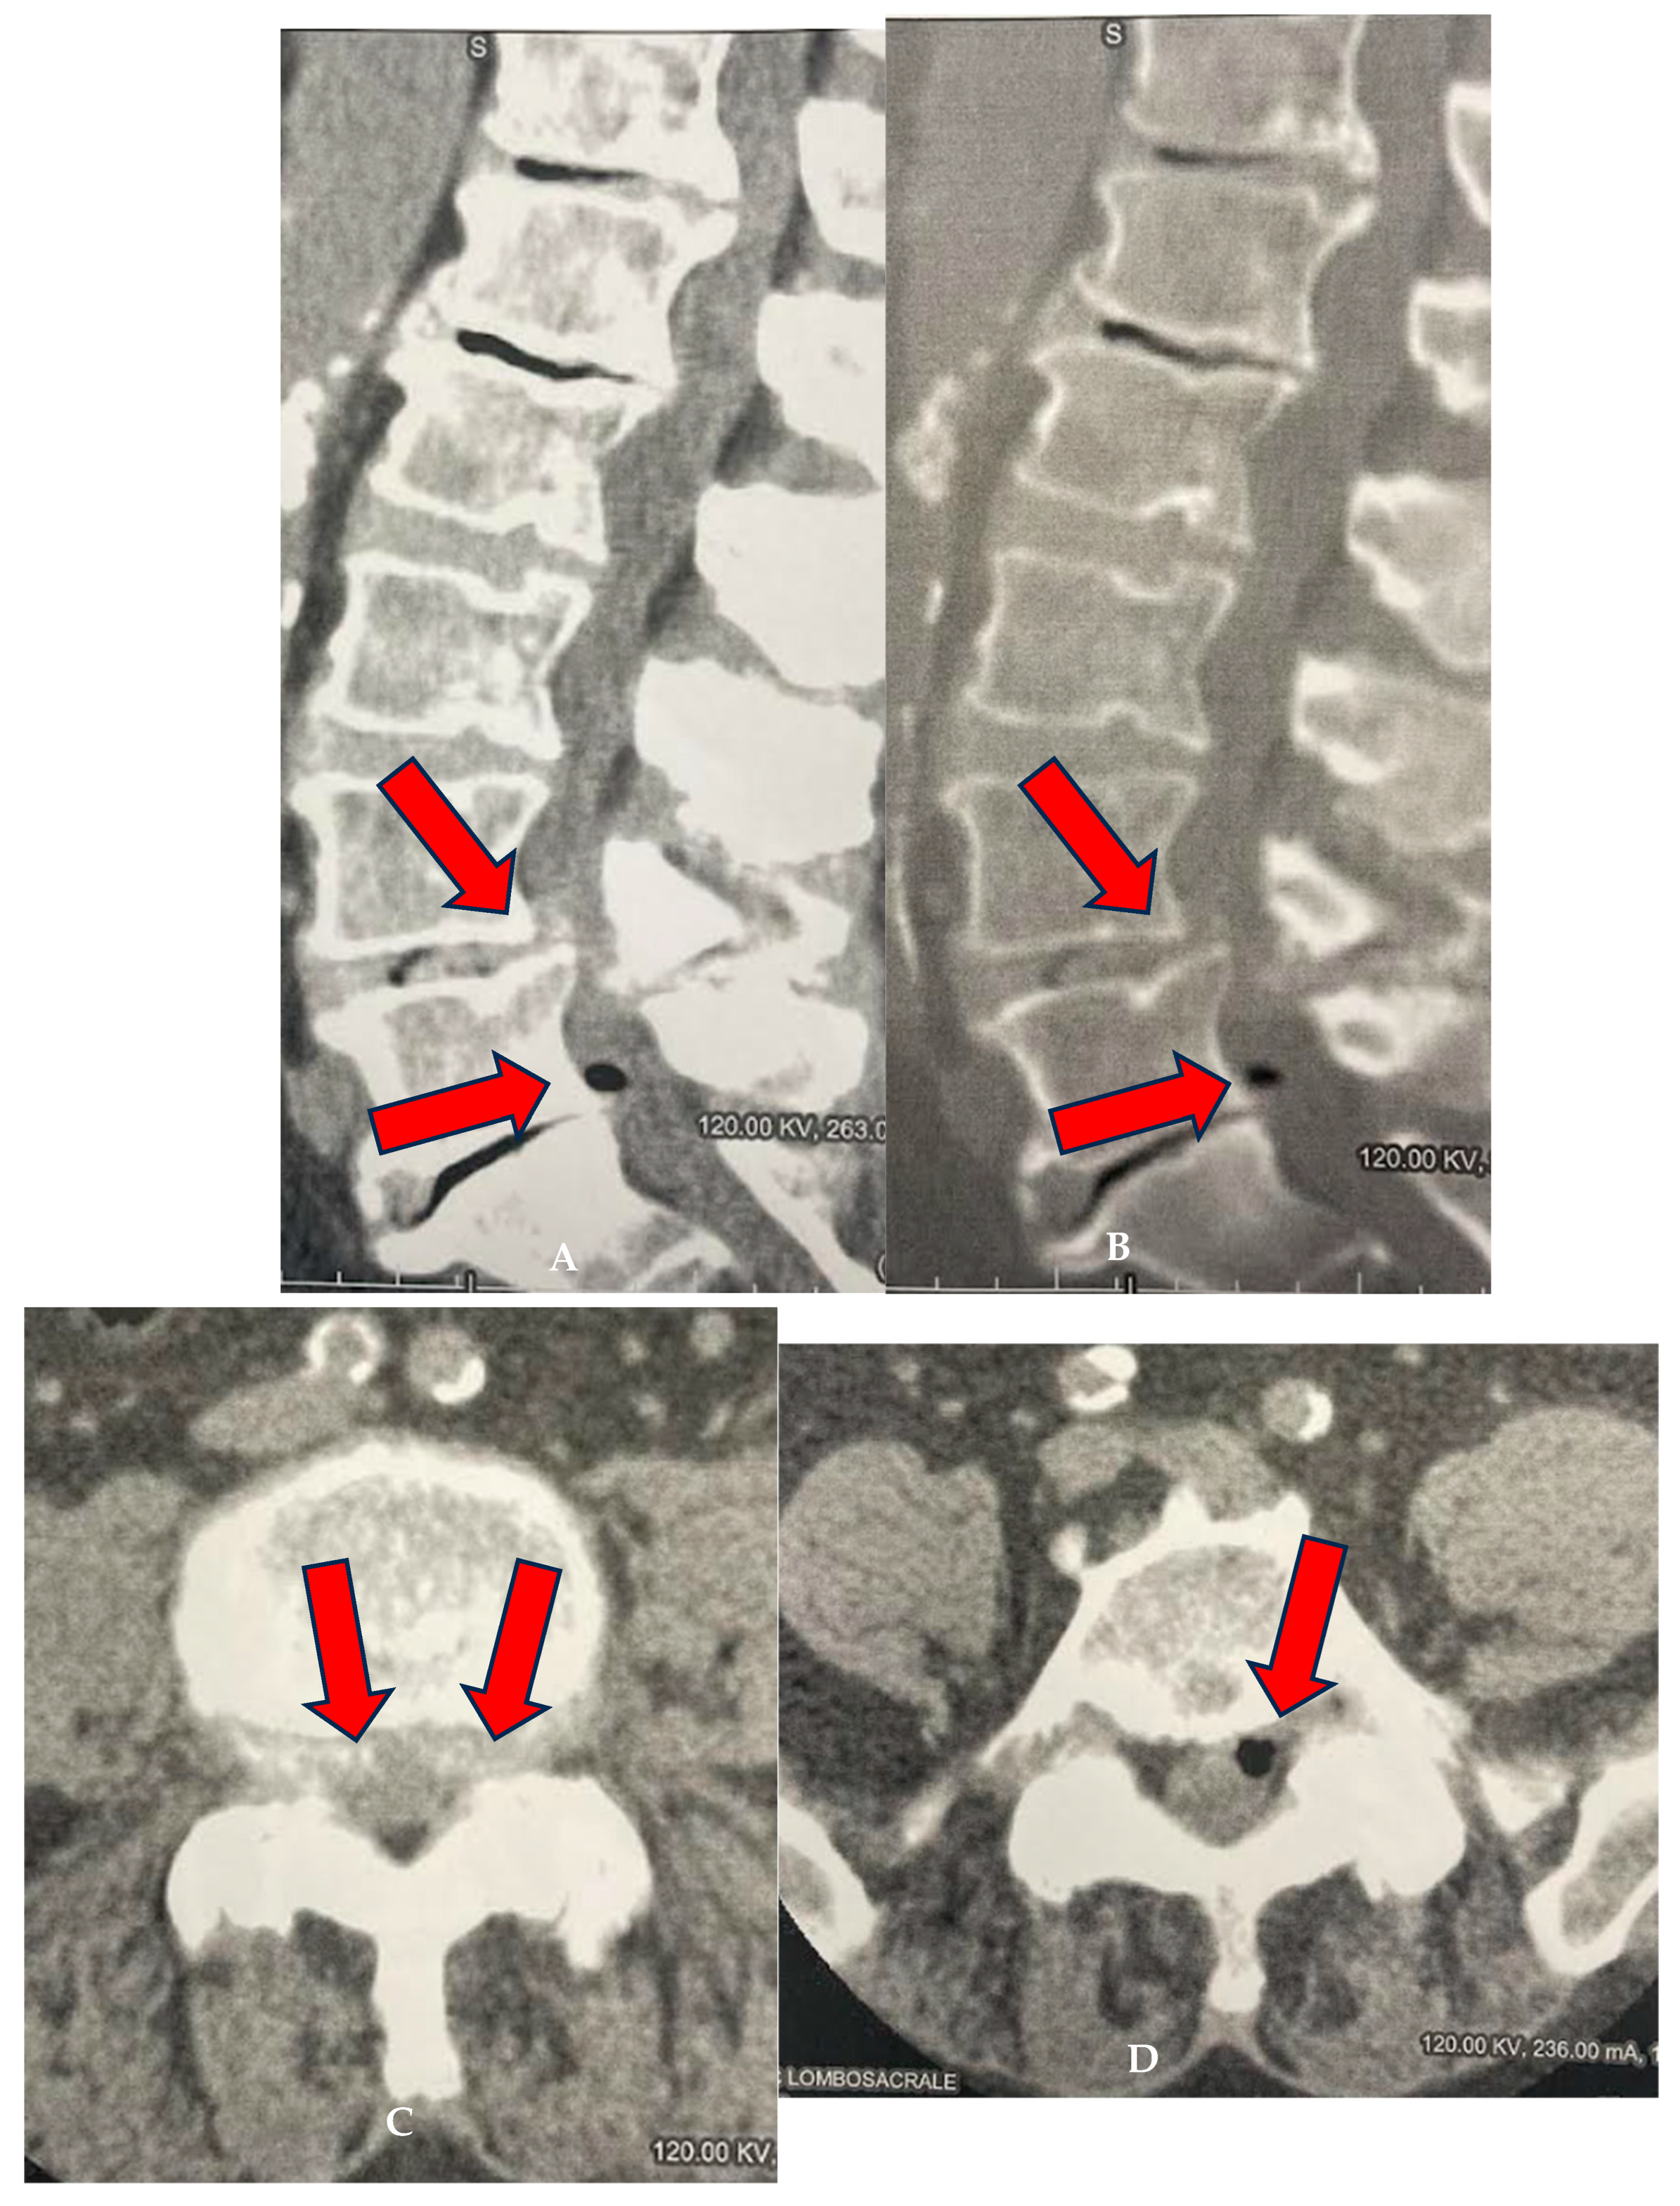

Figure 3.

(A–D): FG of 77-year-old male treated at L4–L5 and L5–S1 levels. (A,B) Sagittal CT reconstructions using algorithms for both parenchyma and bone. L4–L5 spondylolisthesis (arrows), degenerated and thinned L5–S1 disc with vacuolated left paramedian herniation (arrow). (C) Axial CT scan at L4–L5: bilateral paramedian central protrusion of the annulus (arrows). (D) Axial scan at L5–S1: partially vacuolated left paramedian herniation causing indentation on the emergence of the left S1 nerve root (arrow).